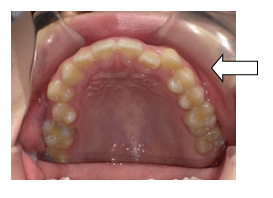

① 上下顎右側 側切歯の反対咬合

② 上顎右側 犬歯 八重歯

③ 上顎左側 第2小臼歯 内側に転位している。